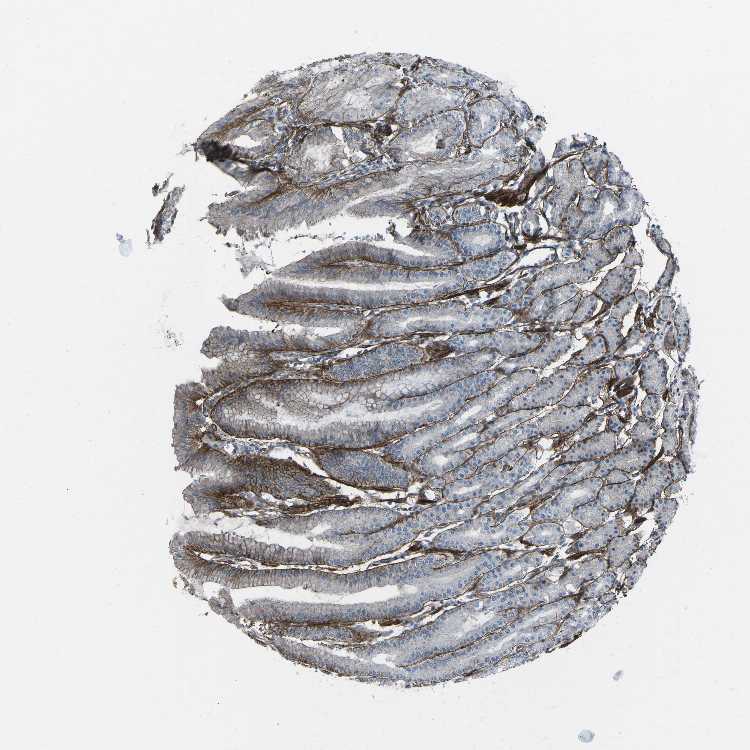

STOMACH - HPA RNA-seqi

The RNA-seq details section shows detailed information about the individual samples used for the transcript profiling and results of the RNA-seq analysis.

Information about each individual sample is listed below, including gender, age, a tissue section image and estimated fractions of cell types. nTPM (normalized transcripts per million) values give a quantification of the gene abundance which is comparable between different genes and samples.

Female, age 33

Stomach sample 61

nTPM: 19

Cell types%

Glandular cells:

60

Smooth muscle cells:

5

Other cell types:

35